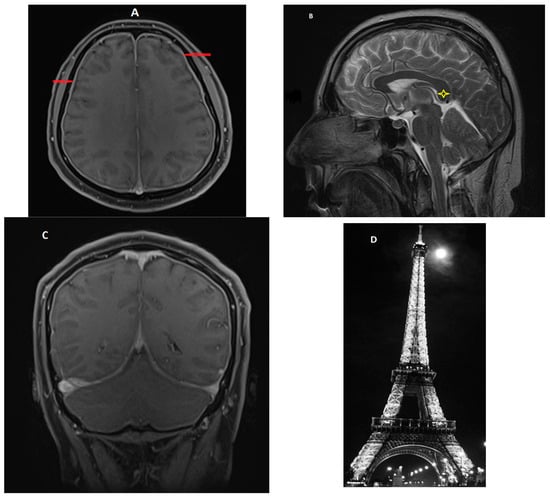

- Signs of brain sagging include flattening of the ventral pons, effacement of the prepontine and perichiasmatic cisterns, or downward displacement of the cerebellar tonsils and brain stem [5,8], which may mimic Chiari type 1 malformation. However, in SIH, the tonsils maintain normal shape and do not descend more than 5 mm below the foramen magnum [37]. Moreover, the findings associated with syringomyelia would argue for the diagnosis of Chiari type 1 malformation [32].

- Pituitary gland hyperemia leads to enlargement of the gland and can be mistaken for a pituitary adenoma [5].

- Reduced optic nerve sheath diameter and thickness (normal—4.4 mm; reduced to a mean of 3.4 mm) is best measured on coronal T2-weighted images or with transorbital ultrasonography [38].